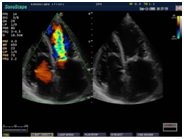

В Медицинском центре «АКВА МЕД МАРИН» проводится УЗИ-диагностика на новейшем ультразвуковом диагностическом сканере Экспертного класса SonoScape S40Exp, в том числе и УЗИ детям с применением специальных детских датчиков. Цветной допплер помогает точной диагностике патологии сосудов и сердца у детей.

- Щитовидная железа - Молочная железа - Нейрохиругия - Кардиология |

Компания SonoScape уделила особое внимание допплеровским режимам и является экспертом в своем классе, что позволяет с легкостью, но в то же время с уникальной точностью проводить исследования с постановкой наиболее точного диагноза.